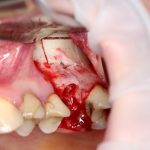

Как это делается, написано здесь>> и здесь>>, при этом существует ошибочное мнение, что большие апертуры доступа в верхнечелюстную полость тяжело заживают и оставляют дефекты кости. Покажу вам пример такого заживления.

Первая операция — мы не можем сразу поставить имплантат из-за почти полного отсутствия кости между полостью рта и дном верхнечелюстной пазухи:

Как видите. восстанавливается всё очень легко, никаких дефектов не остаётся, но при этом мы получаем важное преимущество: достаточную свободу движений при формировании субантральной полости и хороший визуальный контроль за состоянием слизистой оболочки. Никакая нажопная оптика или суперпупермикроскоп, к сожалению, не обеспечат подобный контроль при закрытом синуслифтинге. Да, операция получается травматичнее и масштабнее, чем «закрытый» синуслифтинг, но несёт в себе гораздо меньше рисков.